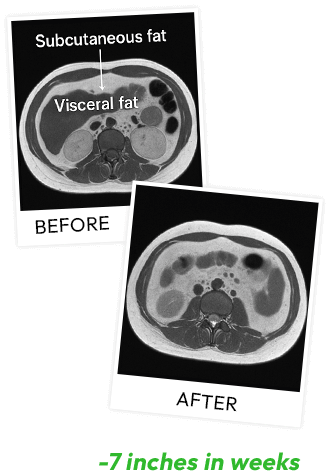

MRI imaging revealed the real story.

These people were losing the worst kind of fat.

The kind that wraps around your organs and fuels chronic disease.

In just weeks, they lost nearly four inches of visceral fat...

And another three inches of subcutaneous fat.

Seven total inches from their midsection ... gone.

The placebo group?

Zero change.